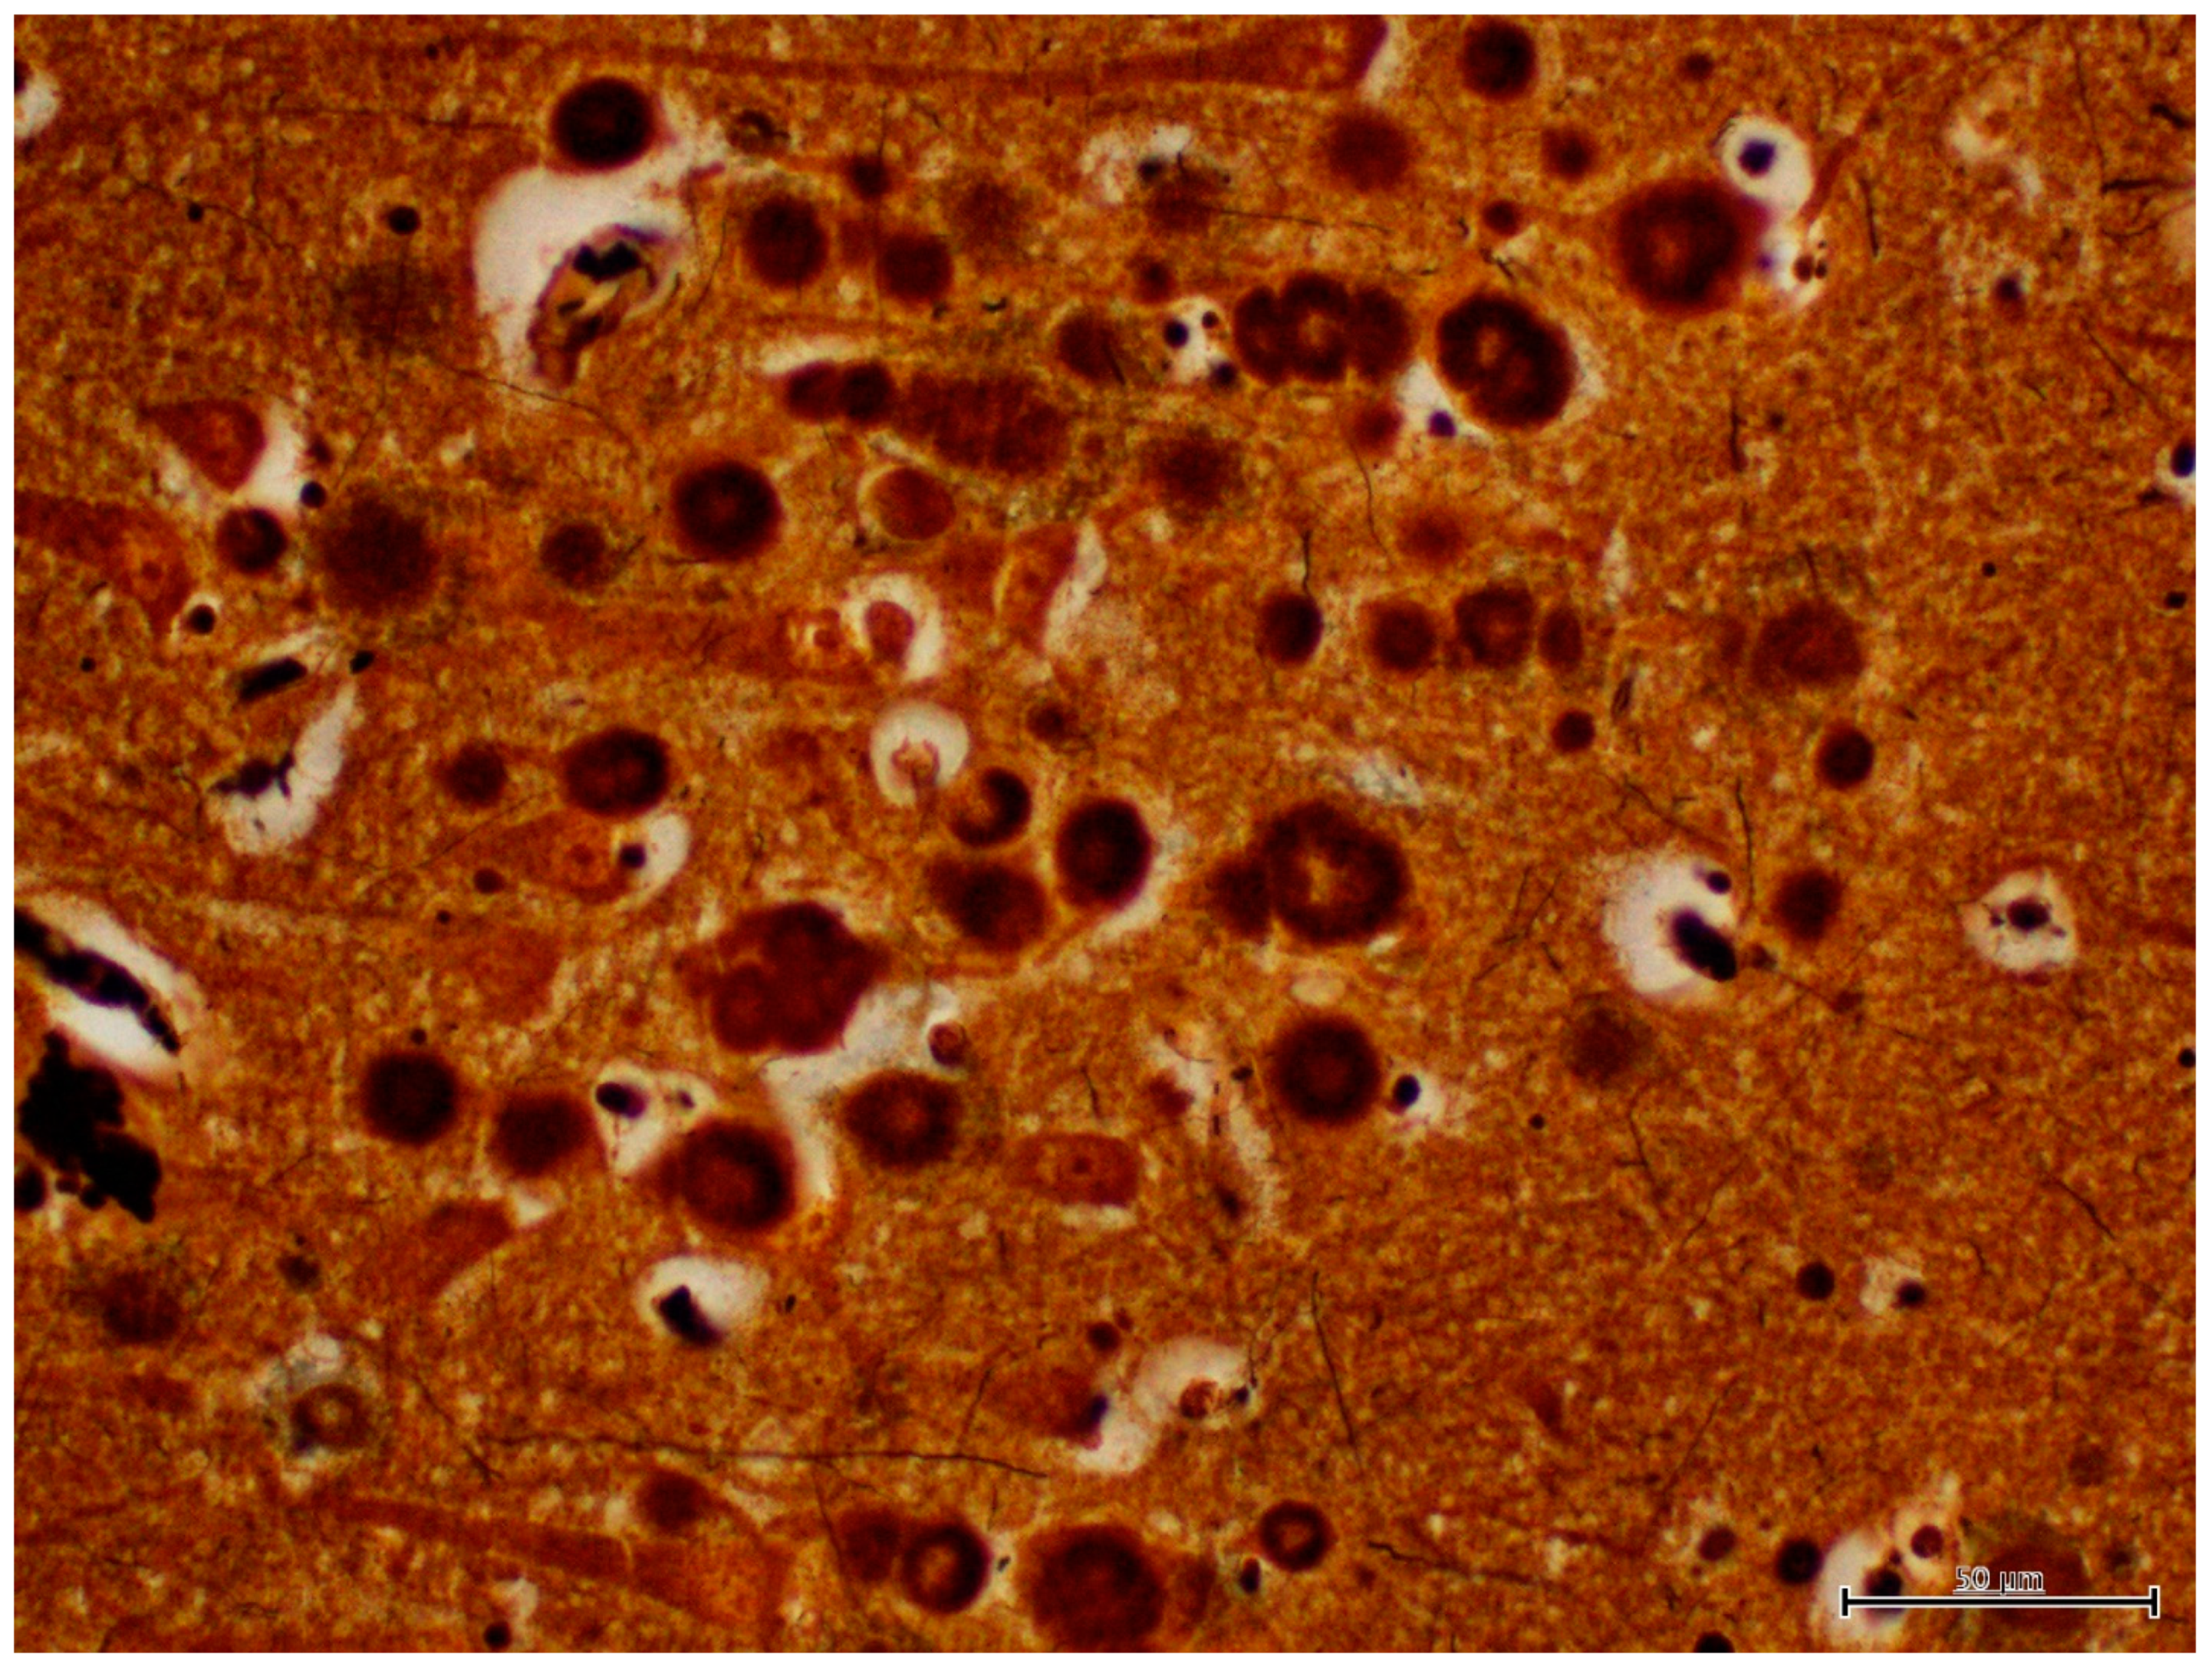

Figure 8.

IHC labeling using α-synuclein monoclonal antibodies to label α-synucleins in the neuropil of the hippocampus.

The results of immunohistochemistry using α-synucleins demonstrated numerous intra- and extra-cellular protein aggregates that positively stained with the neurons, glial cells, neuronal process of CA3 and CA4, subiculum, and white matter of the hippocampus of Moose 1 (Table 1; Figure 8). Minimal staining was noted in the subiculum and white matter of the hippocampus Moose 2. (Table 1). PGBs were consistently negative for α-synuclein antibody staining (Table 1). Ultrastructural examination of coarsely granular material stained positive with a Bielschowsky stain, and α-synuclein antibodies (as shown in Figure 8) in the subiculum; white matter of the hippocampus showed membrane-bound inclusions filled with degenerate organelles interspersed with electron dense bodies (neuromelanosomes), lipid bodies, vesicles, and distorted mitochondria (Figure 9). α-synuclein-positive areas were negatively stained in a GMS test (data not shown).